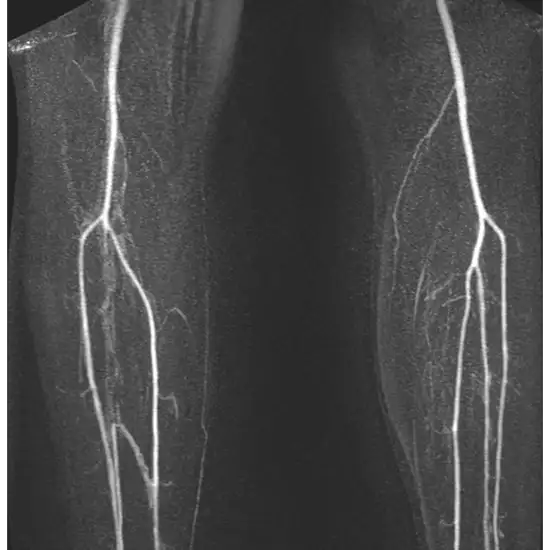

The left thigh's MRA scan can be used to see the thigh bone and the soft tissues like cartilage, tendons, ligaments, muscles, and blood arteries surrounding it. MRA thigh is used to identify the source of leg pain and thigh bone fracture.